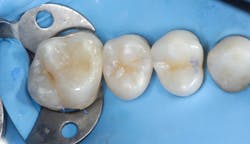

In addition to optimal bonding, the rubber dam may retract the tissues when placed properly, improving our visualization of finish lines, margins, and adhesive materials. One of dentistry’s rubber dam advocates, Dr. Hunter Brinker (the inventor of the B1-B6 clamps), often said “to see is to know” when referring to the benefits of the rubber dam to improve attention to detail through better visual access. It is interesting to note that when the rubber dam is properly placed, it will not only retract the tongue, lips, and cheeks, but it will also atraumatically retract the gingiva, typically 2–3 mm, and expose areas that could not be visualized by any other nonsurgical means (figures 3–5).